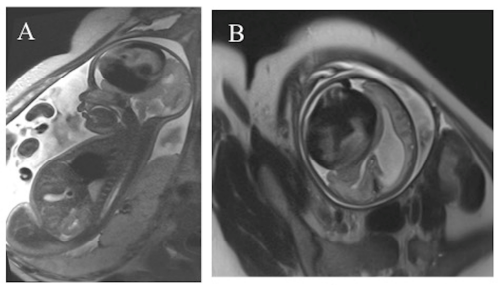

孕28周30岁孕妇接受常规产前检查时,超声检查发现胎儿颅内存在直径7厘米的球形病灶,几乎占据大脑半球的二分之一空间。彩色多普勒超声显示病灶内部存在血流信号,进一步行胎儿核磁共振检查...